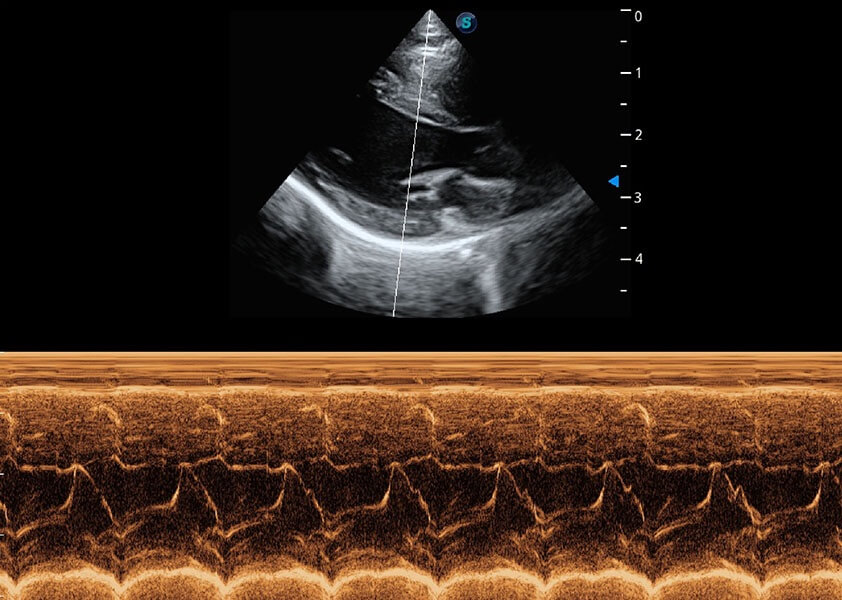

ProPet 60 作为一款高端台式动物超声设备,为动物医生的日常诊断提供了一系列贴合动物临床需求、解决临床实际问题的高级成像功能。凭借全系列高清探头,满足医生对腹部、心脏、生殖、浅表、肌骨等成像的所有需求,切实帮助您提升检查效率,提高诊断信心。

兽用彩色多普勒超声诊断系统

动物是人类最亲密的朋友和最值得信赖的伙伴。银河优越会也一直致力于探索动物专用的超声影像解决方案。 全新推出的ProPet系列,是银河优越会在动物超声影像智能化、专业化、精准化的一次跨越式革新。动物不能用言语来表述自己的不适,通过超声影像,ProPet系列搭建了动物医生与不同物种沟通的“桥梁”,为动物医生注入了“治愈之力”。